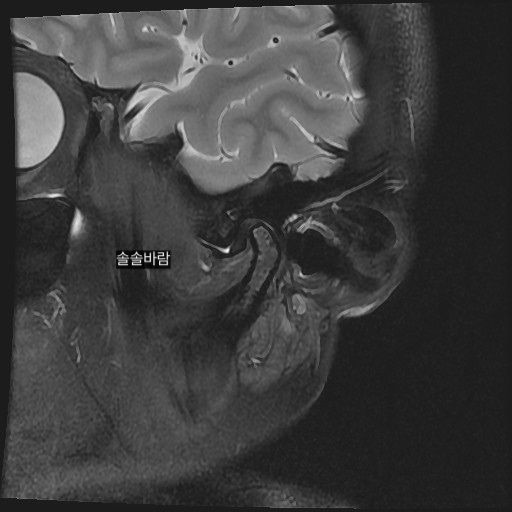

구강내과 턱 MRI 어느 사진이 우측? 좌측?인지 어떻게 보나요? 디스크 두꺼워짐 심한가요?ㅜ

구강내과 턱 MRI 사진 보는데 귀 위치가 다 똑같아서요

어느 사진이 우측? 좌측?인지 어떻게 보나요?

그리고 사진 상 디스크 두꺼워짐 심한가요?ㅜ

현재 사진만으로는 정확히 왼쪽이나 오른쪽이다 라고 할 수 없습니다. 이는 데이터 상의 reference가 필요하며 보통은 해당 부위가 질문자님 기준으로 좌측일 가능성이 가장 크나 이는 좌우 반전을 할 수 있기 때문에 무조건 좌측이라고 할 수 없습니다. 현재 개구시와 폐구시에 보았을 때 condyle (아래턱 부위의 일부)가 disc를 넘어가지 못하고 있으며 이러한 경우 개구제한이 있거나 넘어가더라도 소리가 나면서 넘어갈 수 있습니다. 일부 염증도 보이고 있으므로 내과적인 치료를 하셔야 할 것으로 보입니다.